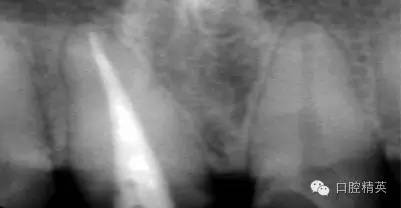

根管治療更是牙體修復(fù)的基礎(chǔ),根據(jù)術(shù)前診斷,對需要做根管治療的或有必要重新做根管治療的,一定要做到恰充,消除隱患,避免將來冠修復(fù)好后,出現(xiàn)根尖炎癥的問題(見圖3、4、5)。在基礎(chǔ)工作做好后,接下來開始牙體預(yù)備,根據(jù)跟個人習(xí)慣,選擇合適的車針(圖6、7)。